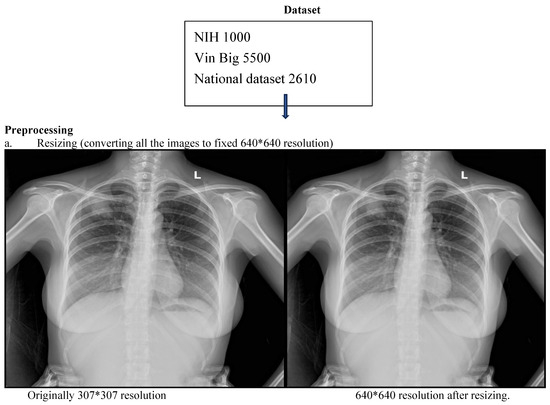

Diagnostic Accuracy of an Offline CNN Framework Utilizing Multi-View Chest X-Rays for Screening 14 Co-Occurring Communicable and Non-Communicable Diseases

Background: Chest radiography is the most widely used diagnostic imaging modality globally, yet its interpretation is hindered by a critical shortage of radiologists, especially in low- and middle-income countries (LMICs). The interpretation is both time-consuming and error-prone in high-volume settings. Artificial Intelligence (AI) [...] Read more.

Background: Chest radiography is the most widely used diagnostic imaging modality globally, yet its interpretation is hindered by a critical shortage of radiologists, especially in low- and middle-income countries (LMICs). The interpretation is both time-consuming and error-prone in high-volume settings. Artificial Intelligence (AI) systems trained on public data may lack generalizability to multi-view, real-world, local images. Deep learning tools have the potential to augment radiologists by providing real-time decision support by overcoming these. Objective: We evaluated the diagnostic accuracy of a deep learning-based convolutional neural network (CNN) trained on multi-view, hybrid (public and local datasets) for detecting thoracic abnormalities in chest radiographs of adults presenting to a tertiary hospital, operating in offline mode. Methodology: A CNN was pretrained on public datasets (Vin Big, NIH) and fine-tuned on a local dataset from a Nepalese tertiary hospital, comprising frontal (PA/AP) and lateral views from emergency, ICU, and outpatient settings. The dataset was annotated by three radiologists for 14 pathologies. Data augmentation simulated poor-quality images and artifacts. Performance was evaluated on a held-out test set (N = 522) against radiologists’ consensus, measuring AUC, sensitivity, specificity, mean average precision (mAP), and reporting time. Deployment feasibility was tested via PACS integration and standalone offline mode. Results: The CNN achieved an overall AUC of 0.86 across 14 abnormalities, with 68% sensitivity, 99% specificity, and 0.93 mAP. Colored bounding boxes improved clarity when multiple pathologies co-occurred (e.g., cardiomegaly with effusion). The system performed effectively on PA, AP, and lateral views, including poor-quality ER/ICU images. Deployment testing confirmed seamless PACS integration and offline functionality. Conclusions: The CNN trained on adult CXRs performed reliably in detecting key thoracic findings across varied clinical settings. Its robustness to image quality, integration of multiple views and visualization capabilities suggest it could serve as a useful aid for triage and diagnosis. Full article

Show Figures

Figure 1